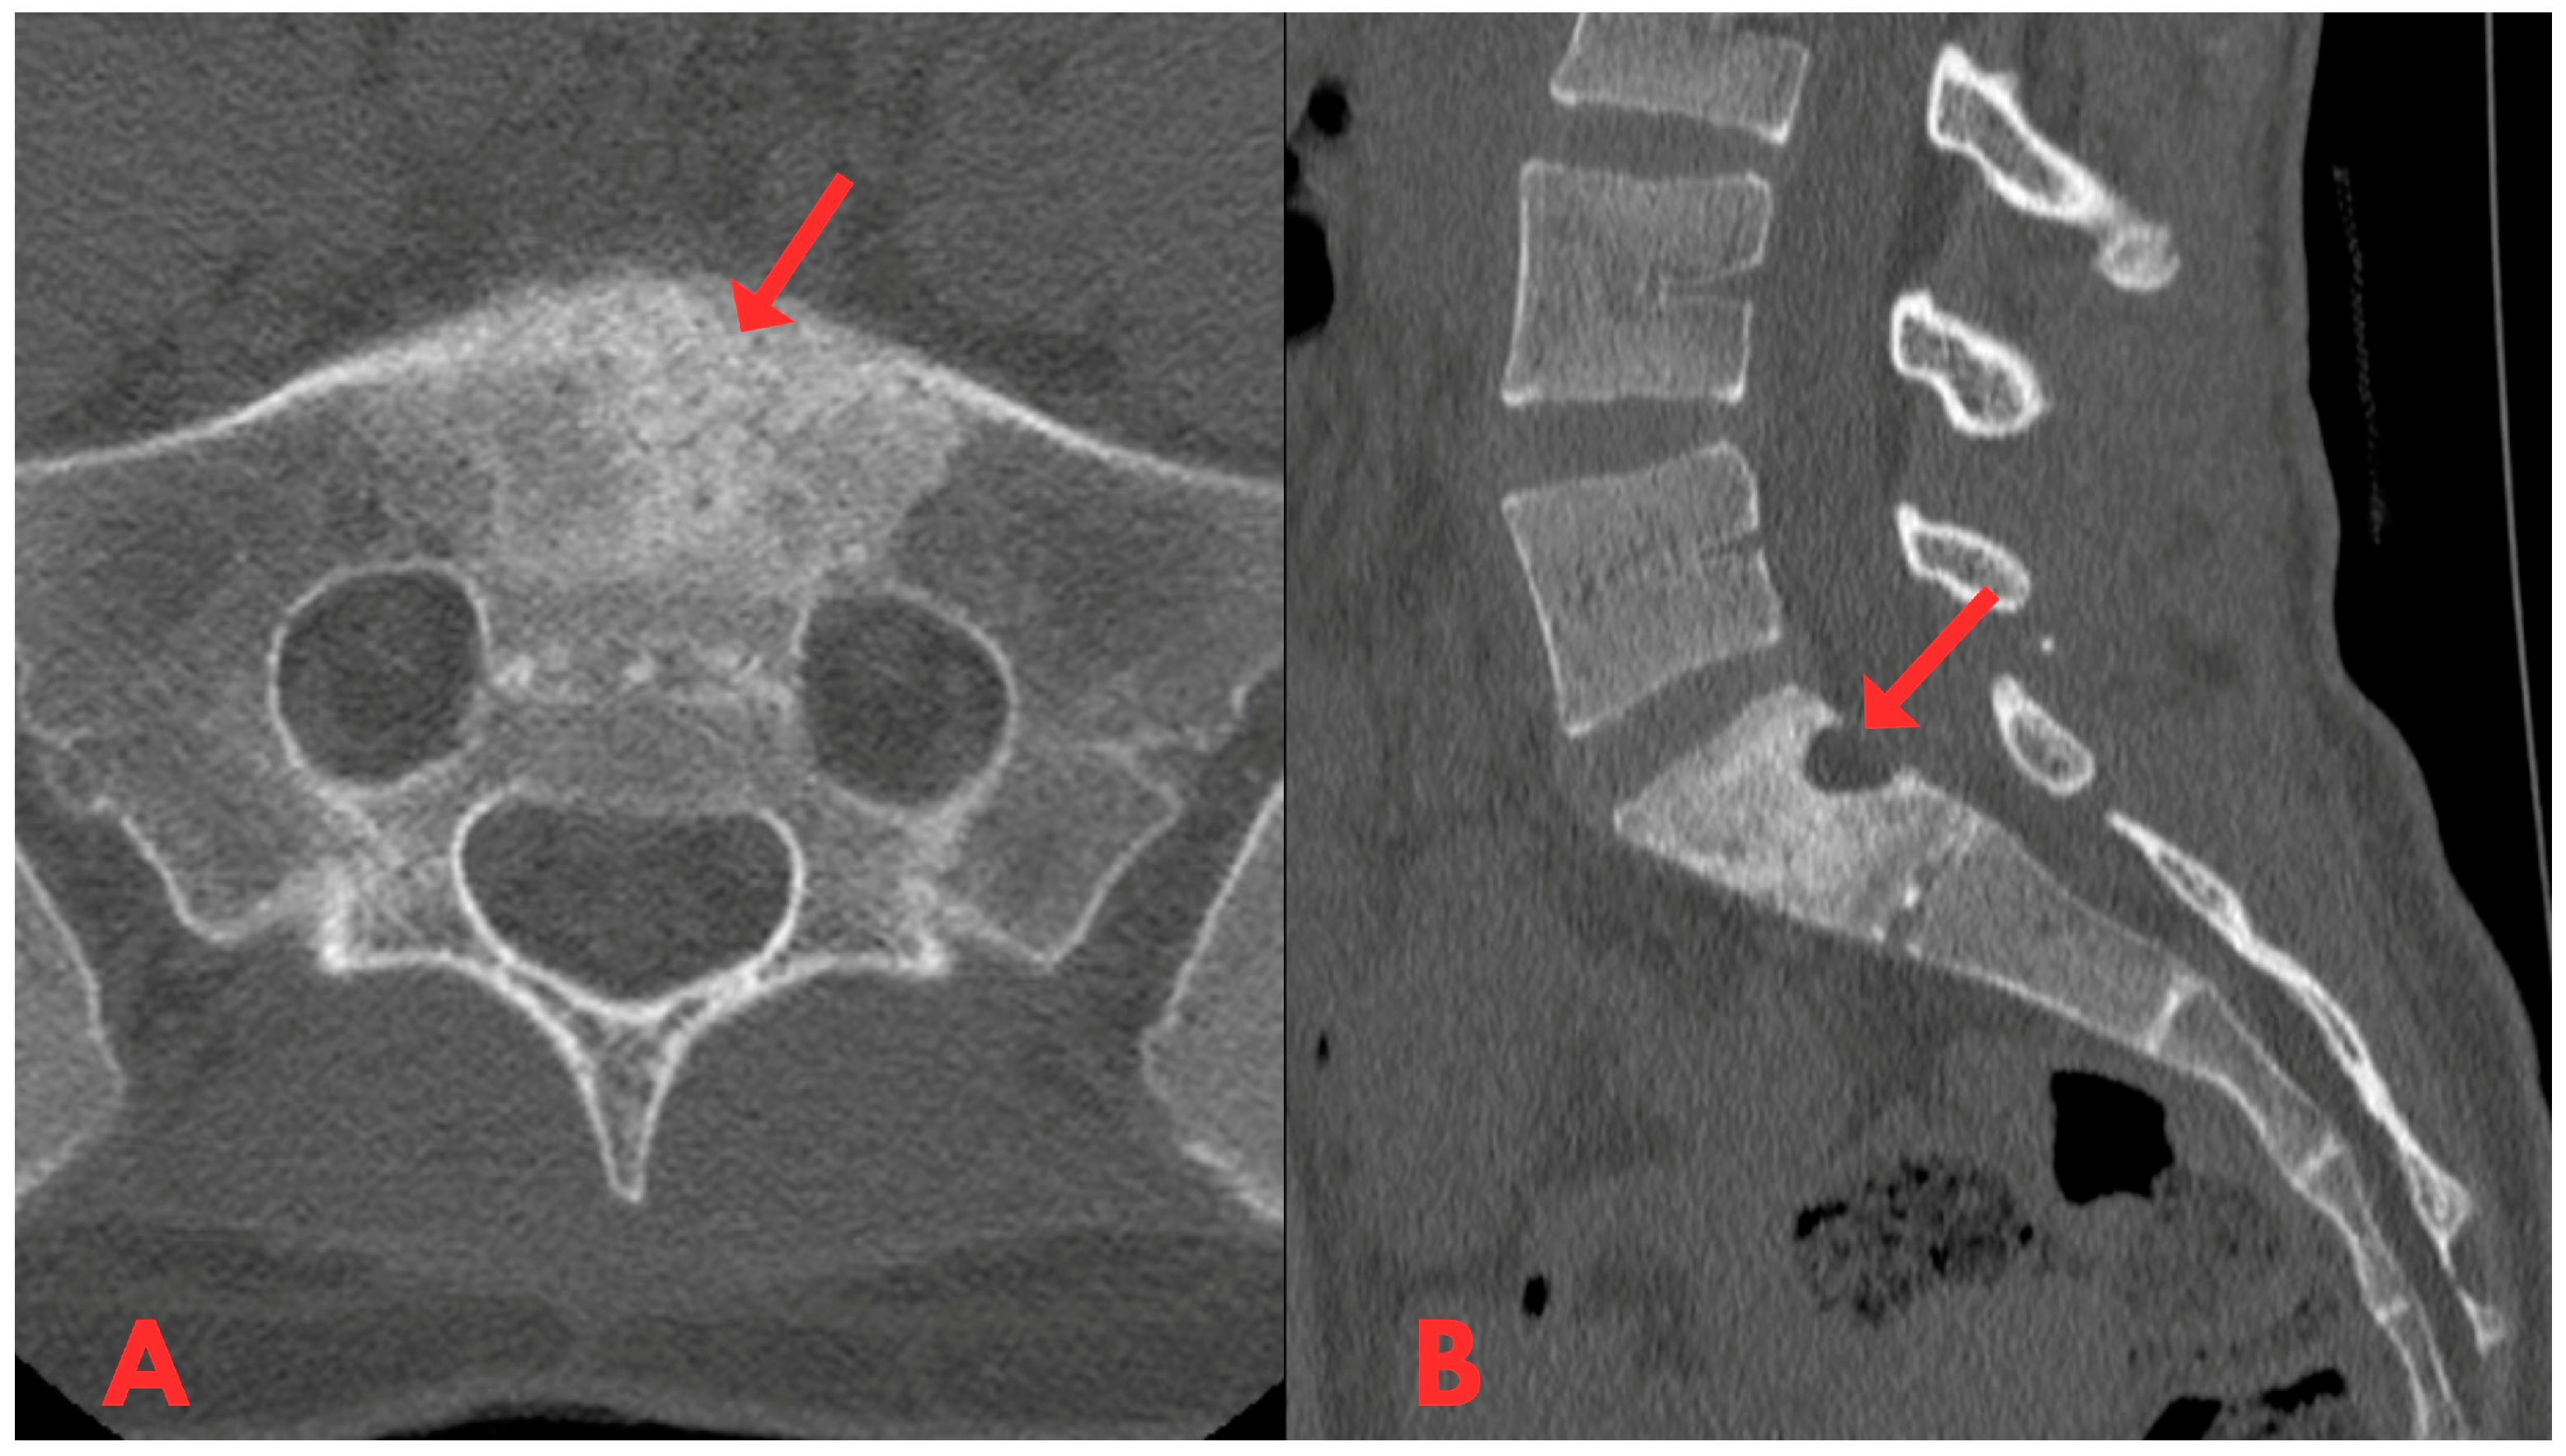

A follow-up CT examination of the lumbar spine was performed (Figure 9), and compared to the previous CT and MRI scans, there were no significant changes in the dynamics of the radiological image.

Figure 9.

A follow-up CT examination of the lumbar spine axial and sagittal planes showing heterogeneous sclerotic changes in the body of the S1 vertebra, and compared to the previous CT and MRI scans, there were no significant changes in the dynamics of the radiological image. The posterior part of the S1 vertebral body shows a small defect after the biopsy.